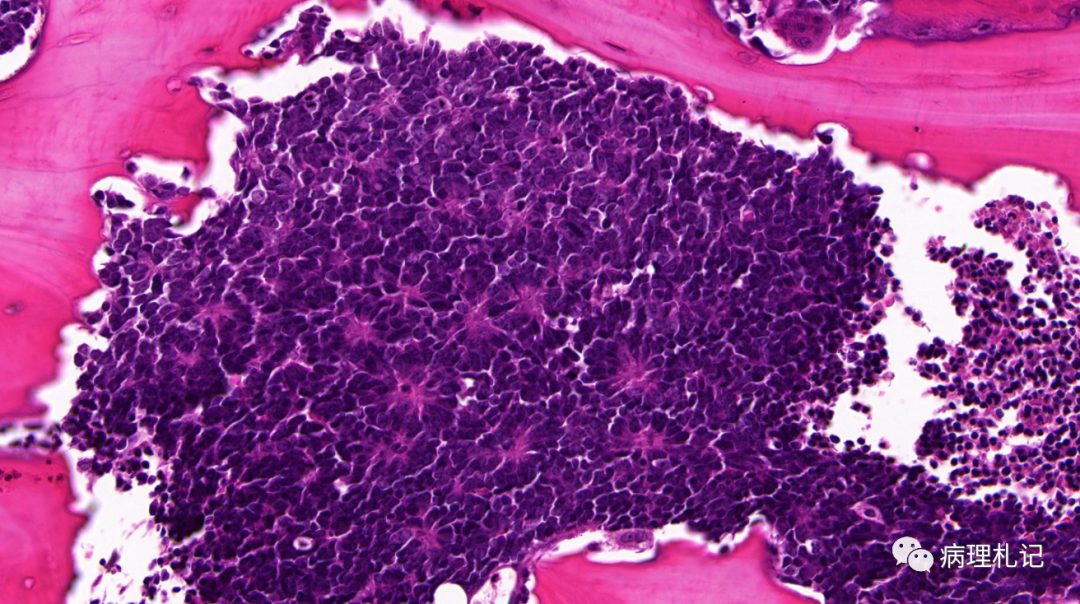

弥漫性神经纤维瘤中惊叹wagnermeissner小体

(1)触觉小体(tactile corpuscle):又称梅氏小体(meissner corpuscle)